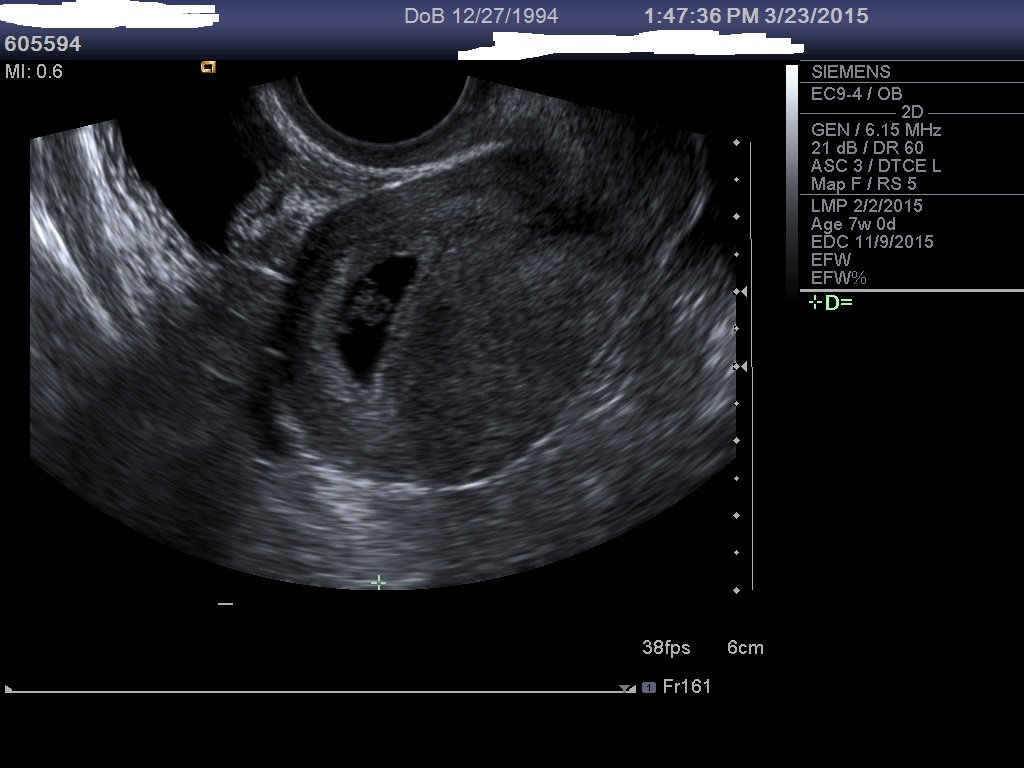

Two pics of the u/s at 7 weeks: